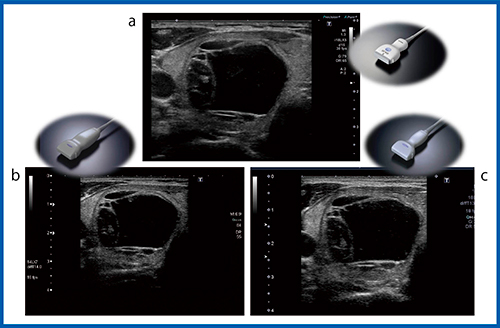

超音波診断装置の進化に伴い検査手技も変化しており,甲状腺のびまん性腫大の検査では,2画面で撮像しても大きな甲状腺の場合には全体が入らず,全体像が把握できないことがあり,甲状腺の全体像をカバーするため水囊を利用して検査を行っていた。現在では,パノラミックビューを用いた検査が可能で,プローブを見たい範囲で横に平行移動させることで,装置が広い断面像を再構築し全体の把握が可能になっている(図1)。

図1 びまん性甲状腺疾患に対するパノラミックビュー

a:水囊で検査した過去画像 b:プローブを平行移動して撮像 c:パノラミックビュー(横断面)

1.基本モードの機種による進化

1)Bモード

図2は囊胞成分を伴う腫瘍で,すべて12MHzプローブを使用している。Aplio XG(b)では正常組織の描出が粗く見えるが,Aplio 500(c)とAplio i800(a)では共に高画質で,明瞭に描出されている。良悪性の評価が必要とされる充実性結節の画像(図3)では,Aplio 500(a)でも境界を含め明瞭に描出されているが,Aplio i800(b)ではコントラスト分解能が高いため腫瘍背側部の境界まで描出が明瞭となり,さらに,高い空間分解能によって全体にやわらかい画像が得られている。

図2 超音波診断装置の進化:Bモード(12MHz)

a:Aplio i800 b:Aplio XG c:Aplio 500

図3 Bモードによる充実性腫瘍の描出能の比較(12MHz)

a:Aplio 500 b:Aplio i800